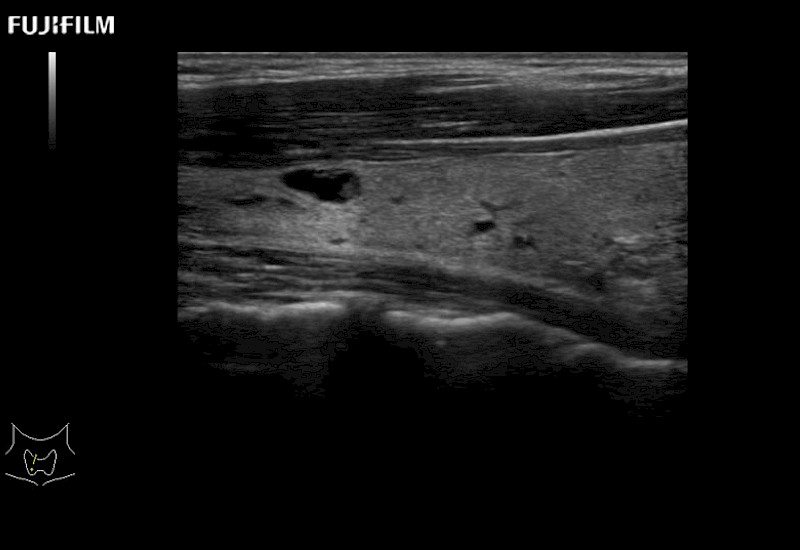

For precise surgical oncology ultrasound imaging, Fujifilm Healthcare offers premium level solutions that include:

Extraordinary high-resolution digital imaging

Multi-Parametric imaging modalities

Our dedication to Surgical Oncology allows us to offer superior image quality, outstanding system reliability and intuitive use of cutting edge technology.

The ARIETTA 750 incorporates all of the proven technologies and functions that medical professionals have come to expect from Fujifilm Healthcare.

ARIETTA 750 is the definitive diagnostic ultrasound solution for any clinical setting - Private Office, Imaging Center, or Hospital. The ARIETTA platform provides the ultimate in clinical performance with its state-of-the-art features and large user-friendly display.

The ARIETTA 650 DI combines trusted Fujifilm Healthcare technologies and features tailored for surgical oncology.

Designed to meet the demands of surgeons, the ARIETTA 650 DI offers precise guidance. Its advanced capabilities and large, intuitive display offer accurate and efficient care in operating rooms and specialized surgical settings.